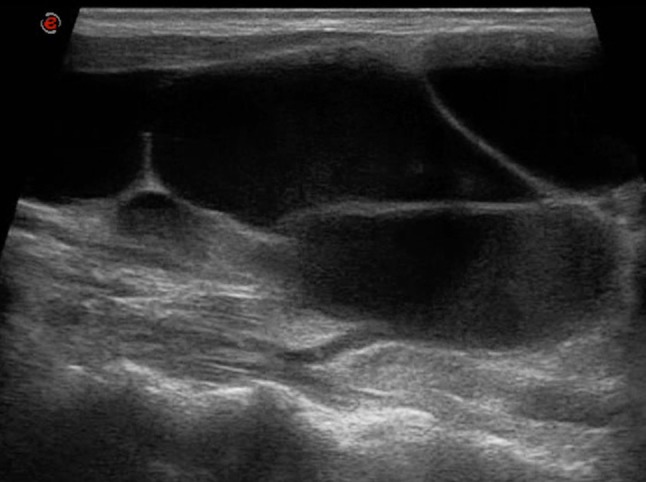

Fig. 3.

Complicated TGDC in a 21-year-old boy, slightly off-midline to the left, between the thyroid cartilage and strap muscles. Transverse B-mode US image (on the left) show a uniformly echogenic, pseudosolid appearance of a TGDC. Note, however, the posterior enhancement, suggesting its cystic nature. No internal flow is observed with CD (in the middle). SE (on the right) shows elasticity in the whole region of interest (homogeneously green with some red areas mixed in), an appearance suggestive of benign lesion. TGDC was confirmed by pathologic examination of surgical specimen, which showed no infection or hemorrhage. Pseudosolid pattern was due to proteinaceous content of cyst